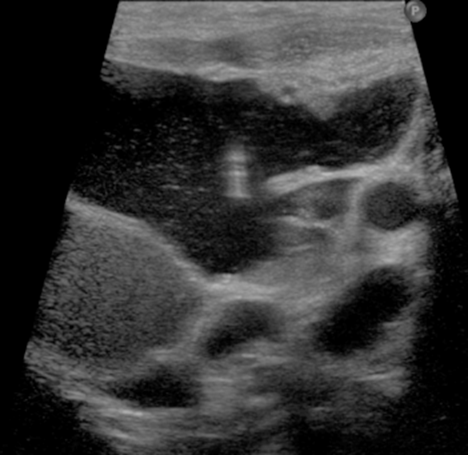

US guided needle placement into a macrocystic lymphatic malformation